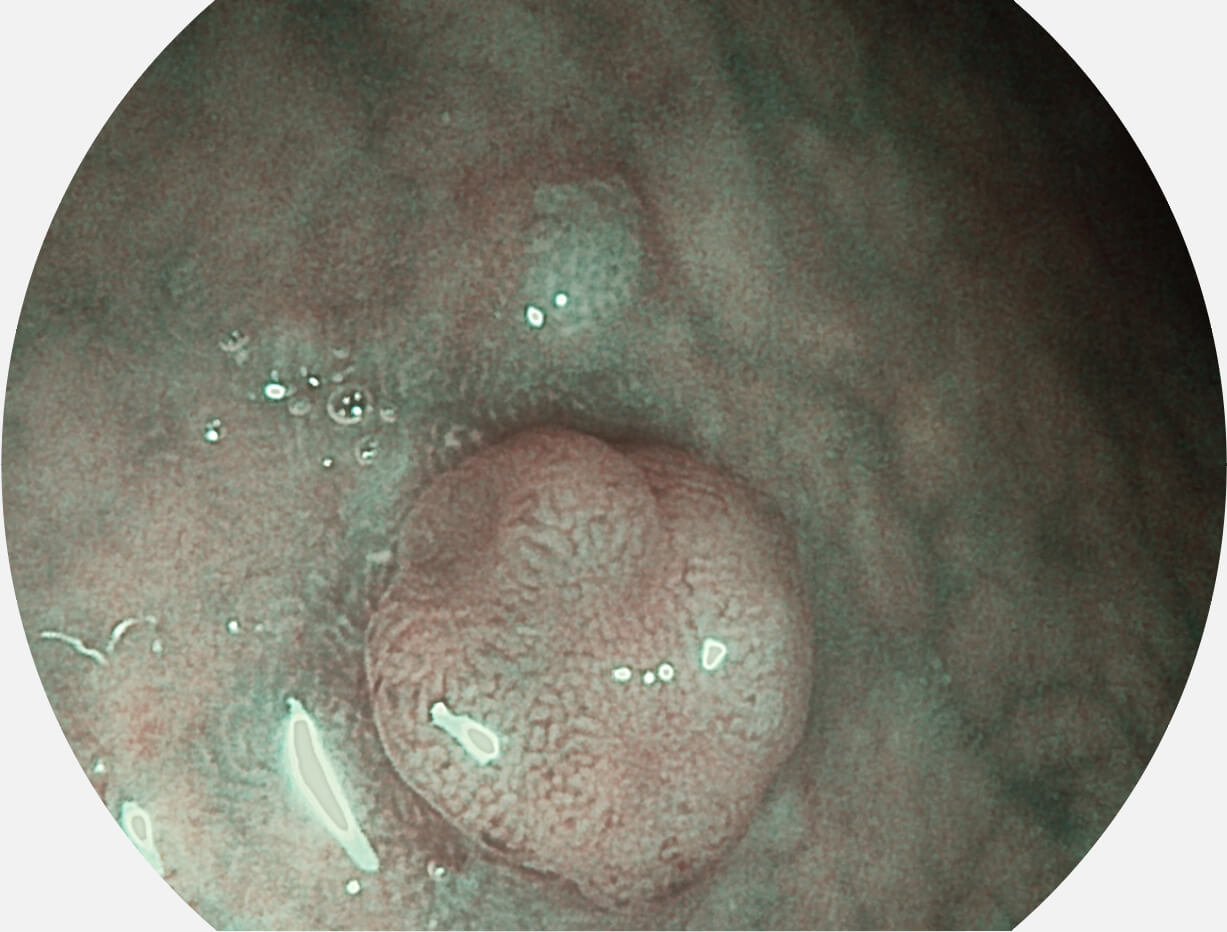

Versatile Intelligent Staining Technology, VIST

强调浅层黏膜结构的同时,保证照明亮度和提升浅层微血管与中层血管颜色对比度,病变边界更清晰。

VIST图像